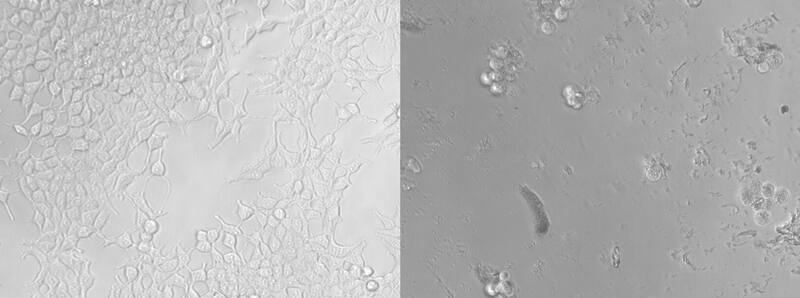

Aunque los efectos en la salud del consumo de micro y nanoplásticos siguen sin estar claros, el equipo de Nebraska descubrió además que tres cuartas partes de las células de riñón embrionarias cultivadas habían muerto después de dos días de haber sido introducidas en esas mismas partículas. Un informe de 2022 de la Organización Mundial de la Salud recomendó limitar la exposición a tales partículas.

Con la ayuda de Svetlana Romanova, del Centro Médico de la Universidad de Nebraska, el equipo cultivó y expuso células embrionarias de riñón a las partículas de plástico reales liberadas de los contenedores, una primicia, por lo que Hussain puede decir. En lugar de introducir solo el número de partículas liberadas por un contenedor, los investigadores expusieron las células a concentraciones de partículas que los bebés y niños pequeños podrían acumular durante días o de múltiples fuentes.